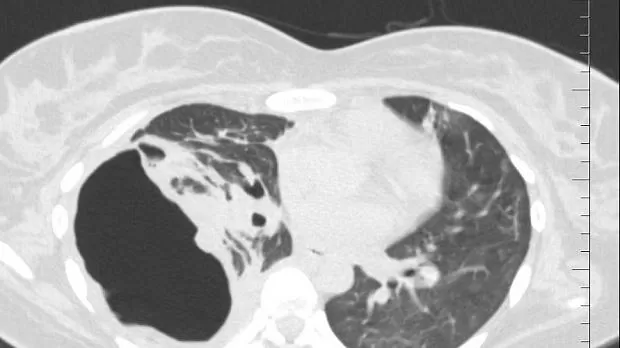

Пациентка переведена к нам в отделение торакальной хирургии из родильного отделения. Будучи беременной на 9 месяце COVID-19 с возникновением двухсторонней вирусно-бактериальной пневмонии с деструкцией в нижней доле правого легкого, эмпиемой плевры и бронхоплевральным свищем. По данным Р-КТ органов грудной клетки: полость деструкции в нижней доле правого легкого. Выполнено дренирование плевральной полости справа. У пациентки – утечка воздуха по дренажу из плевральной полости. 05.06.2020 выполнена клапанная бронхоблокация промежуточного бронха (блокатор Medlung №12) с хорошим клиническим эффектом (сброс воздуха по прекратился через 6 часов после вмешательства). Но, через 2 дня пациентка откашляла блоктор.